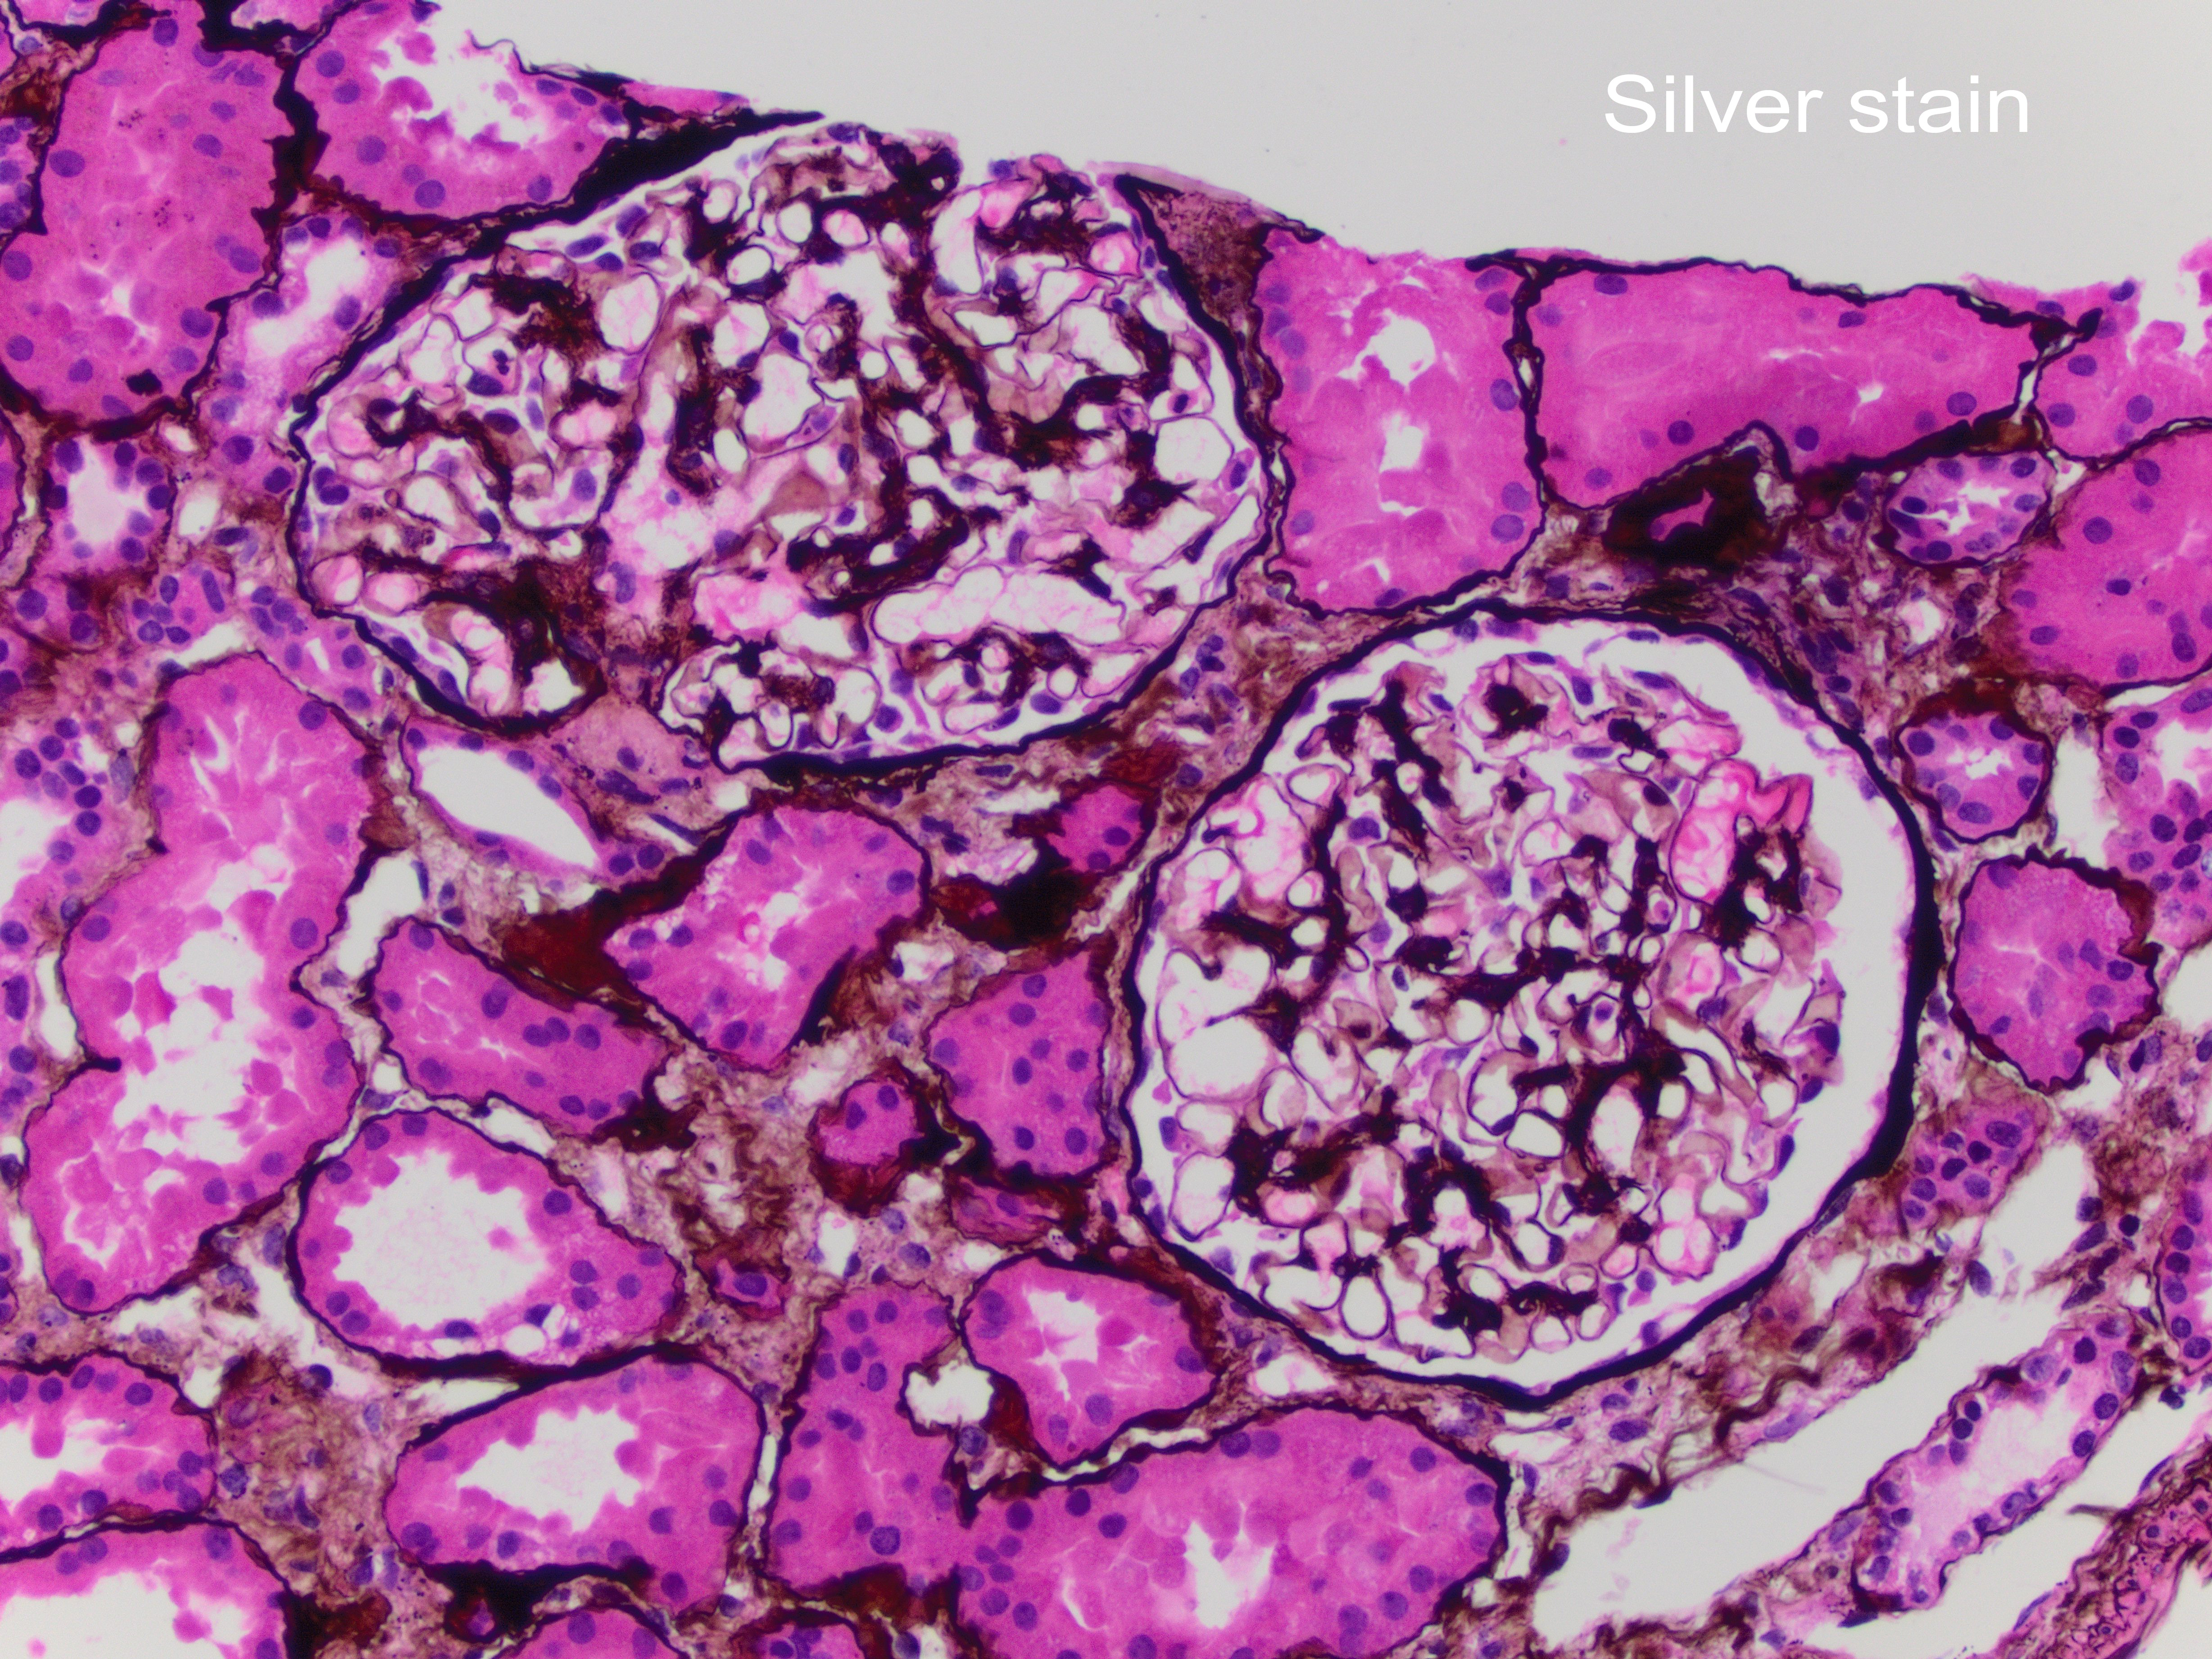

A 42-year-old African-American female with a history of systemic lupus erythematosus with acute kidney injury (creatinine 2.7 mg/dL), proteinuria (1064 mg/24 hr), and no hematuria, was admitted for lupus encephalitis. Renal biopsy by light microscopy showed that most glomeruli had no lesions (Figure 1) with one glomerulus with glomerular tuft collapse, and podocyte hypertrophy/hyperplasia (Figure 2). There was positive mesangial staining by immunofluorescence with IgG, IgM, IgA, C3, C1q, and light chains (Figure 3). Electron microscopy findings included diffuse foot process effacement, and mesangial electron-dense deposits (Figure 4).